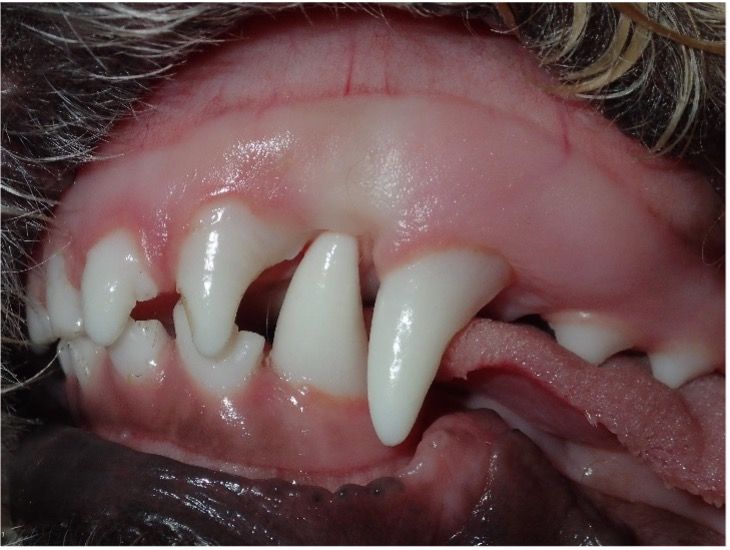

• Poodles and doodles: These breeds can have linguoversion of mandibular canine teeth (Figure 9), also known as base narrow, which often causes occlusal trauma on the roof of the mouth (Figure 10). Early intervention during deciduous and adult tooth stages is crucial.